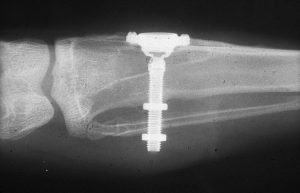

Мы сделали рентгеновские контрольные снимки —  панорамный для оценки положения имплантатов и прицельный для контроля посадки абатментов.

На последнем видно, что абатменты (особенно правого на фото зуба) не сели на свои места, между ними и платформами имплантатов есть щель — и эта ситуация наглядно демонстрирует, ПОЧЕМУ такие снимки необходимы. Мы вернули пациентку в хирургический кабинет и провели коррекцию абатмента (уменьшили ширину трансгингивальной части), После чего, проводили пациентку в кабинет стоматолога-ортопеда для временного протезирования.